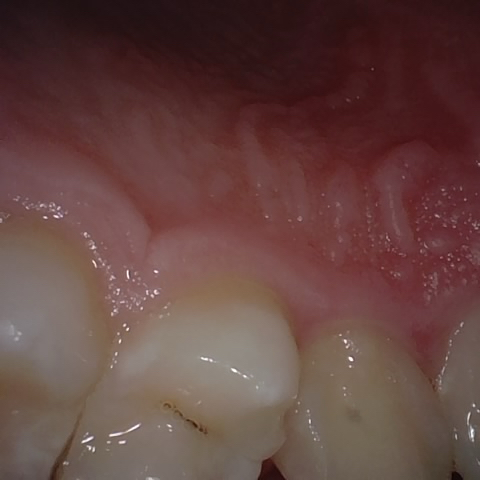

Annotated as "Good"